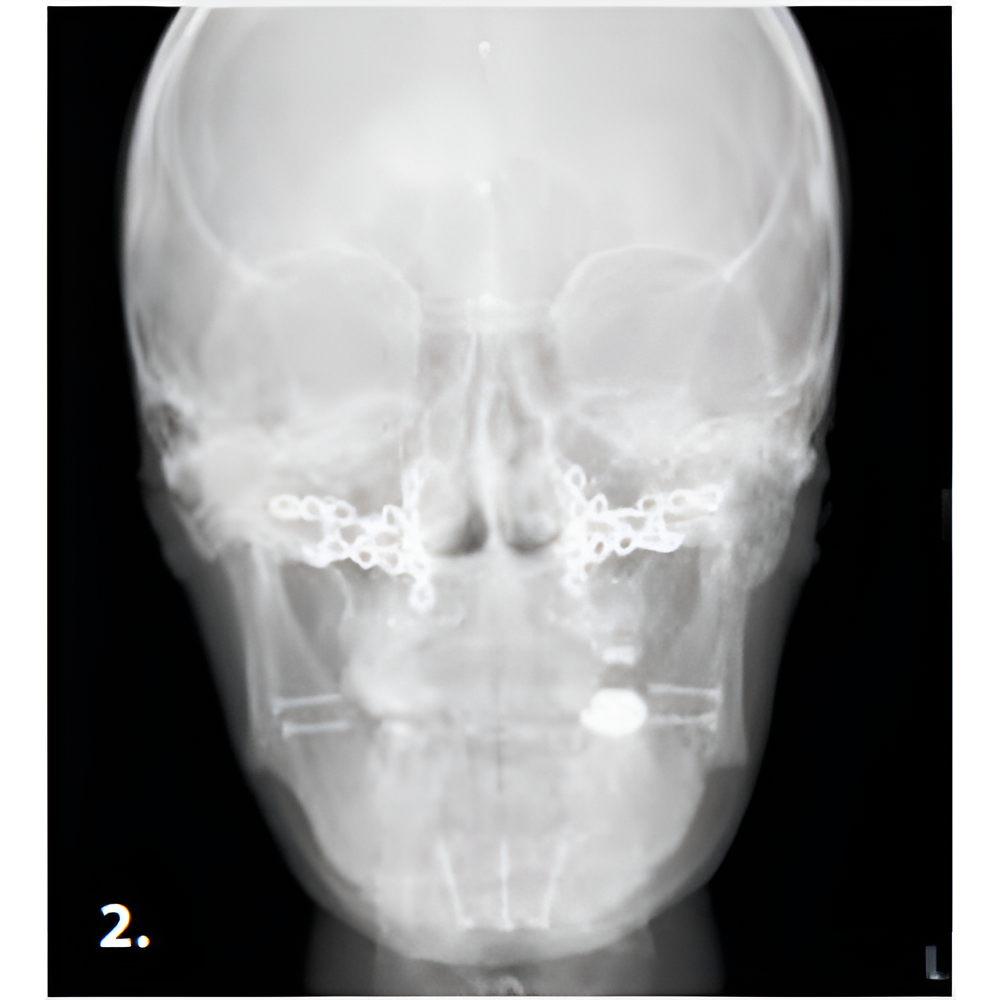

Hyperion X9 pro meets every diagnostic requirement by easily integrating into the work flow and guaranteeing maximum comfort for both patient and operator. SuperHD quality images that allow the doctor to make a correct diagnosis, thanks to easy and completely guided procedures. Full accessibility and user-friendliness with the innovative full-touch control panel and fast Face To Face positioning which guarantees maximum comfort to both patient and operator.

- SuperHD CB3D

- 3D Images

- Outstanding Technology

- Versatile and Precise

- Minimum Dose, Maximum Diagnostic Quality